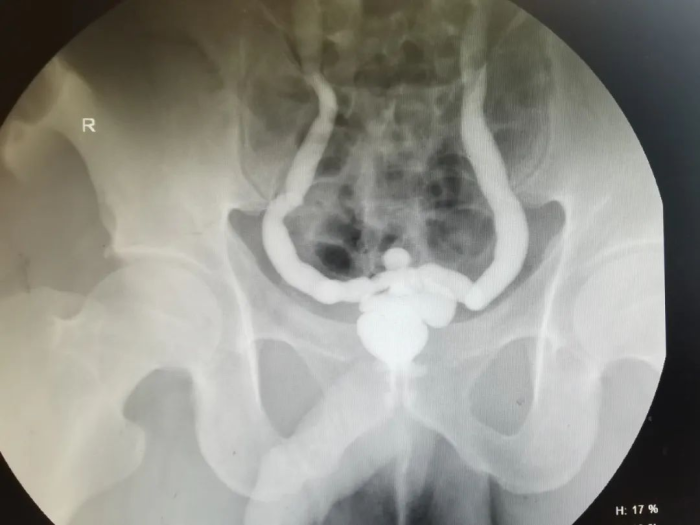

经过科室讨论,泌尿外科主任、主任医师石英、副主任医师李凯、主治医师广雨龙组建治疗团队为患者实施全腹腔镜下乙状结肠膀胱扩大术。经过五个多小时的努力,手术圆满成功,术后患者恢复良好。

2022年底,贵州航天医院泌尿外科就完成了在遵义市首例全腹腔镜下乙状结肠膀胱扩大术,手术效果非常好。当时病例为24岁男性患者,两次排尿间隔仅十几分钟,且每次量很少,反复尿频1年以上就诊贵州航天医院泌尿外科,相关检查显示膀胱最大容量为12ml,被诊断为泌尿系结核、膀胱挛缩。随后,由李凯主刀,实施全腹腔镜下乙状结肠膀胱扩大术,截取肠管缝合成新膀胱,完成患者膀胱扩大术,新膀胱形态正常,无尿漏及其他并发症。

泌尿系结核膀胱挛缩的治疗是泌尿外科公认的难题,金标准是肠道膀胱扩大术。传统手术方式为开放手术,采用腹腔镜辅助处理,在体外进行肠道裁剪及吻合。对于此类膀胱挛缩患者,实施腹腔镜下膀胱扩大术是较好的手术方式。膀胱扩大术也是近年来热点问题。“新膀胱”是一种取15-20cm左右的乙状结肠,将其折叠缝合形成一个新的储尿囊与原挛缩的膀胱吻合以扩大膀胱容量的手术方法,目的在于扩大膀胱容量,减少排尿次数,提高患者生活质量。